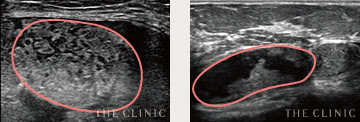

しこりの状態をチェック

オイルシスト

しこり内部の壊死した脂肪がオイル状になっているしこりは、エコーで黒く映し出されます。

充実性

オイル状ではなく脂肪組織が残っているしこりでは、しこりの内部が白っぽく映し出されます。

石灰化

被膜にカルシウムの結晶が沈着したしこりはエコーで投影できず、深部が黒く映ります。

瘢 痕

しこりから壊死脂肪が漏れて炎症すると、しこりが瘢痕化。エコー鑑別が難しい症例です。

治療前

治療後